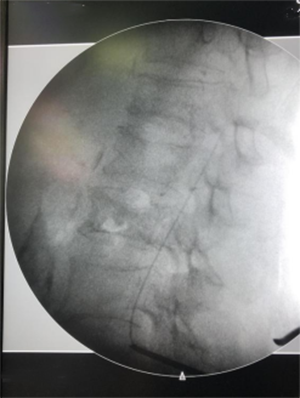

癌痛是癌症患者最常见的并发症之一,剧烈疼痛不仅导致患者生存质量下降,还会使患者抗癌依从性下降,从而影响肿瘤的整体治疗效果。9月6日,中国医学科学院肿瘤医院山西医院(山西省肿瘤医院)神经外科主任冯富强、赵晓军主任医师、王红亮医师以及骨软组织肿瘤科关哲副主任医师、麻醉科李宇副主任医师、那志平主治医师、手术室刘涛、赵君团队为一名直肠恶性肿瘤骨转移患者成功实施了我院第一例椎管内半植入镇痛泵置入手术。

该患者为70岁女性,2021年8月诊断为直肠中分化腺癌,后行放化疗,定期复查。2023年3月自觉左侧肩背部疼痛,尚能忍受,居家口服中药治疗。2023年6月左侧肩背部疼痛加剧,逐渐扩展至左侧腰髋部,难以翻身,不能行动,口服盐酸吗啡片、双氯芬酸钠缓释片、去痛片缓解效果不佳。2023年7月24日到我院神经外科就诊。根据患者具体病情及临床表现,先给予静脉PCA(自控镇痛)治疗,并于9月6日实施椎管内镇痛泵半植入手术,手术顺利,患者对治疗效果满意。

该手术通过植入体内的药物灌注泵,将药物精准注入脊髓蛛网膜下腔,阻断疼痛信号发送至大脑,以口服药物1/300的剂量实现快速镇痛效果。同时降低患者使用盐酸吗啡片等止痛药物的副作用,助力患者减轻疼痛,回归正常生活。本例患者术后效果显著,疼痛评分由NRS 9分降为3分。